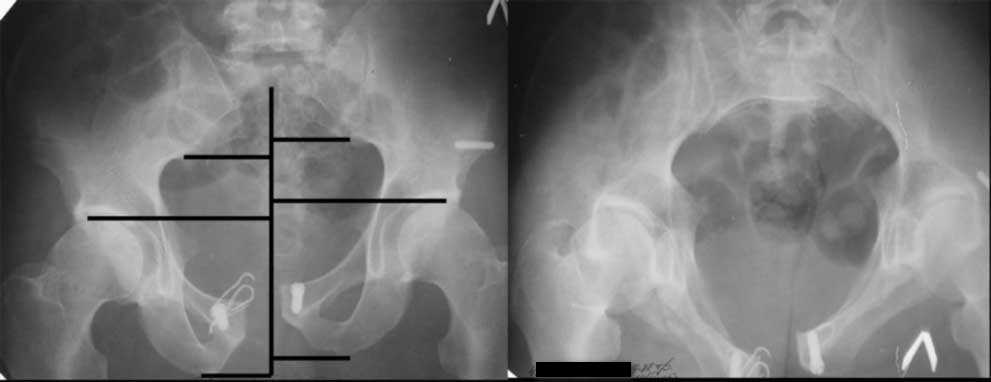

закрытое низведение правой половины таза кольцевым аппаратом (с фиксацией задних отделов), затем проведение илиосакральных винтов, реостеосинтез лонного сочленнения, дальнейшая фиксация в аппрате 2-3 мес. Похожий пример в приложении.